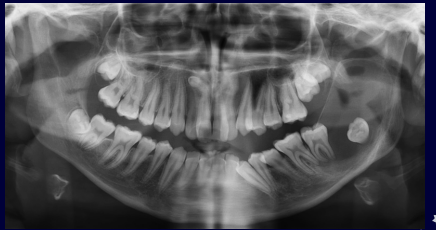

What are the 7 signs of IAN involvement?

1.Darkening of the roots 2.Interruption of the white line 3.Diversion of the mandibular canal 4.Deflection of the roots 5.Narrowing of the roots 6.Dark and bifid roots 7.Narrowing of mandibular canal